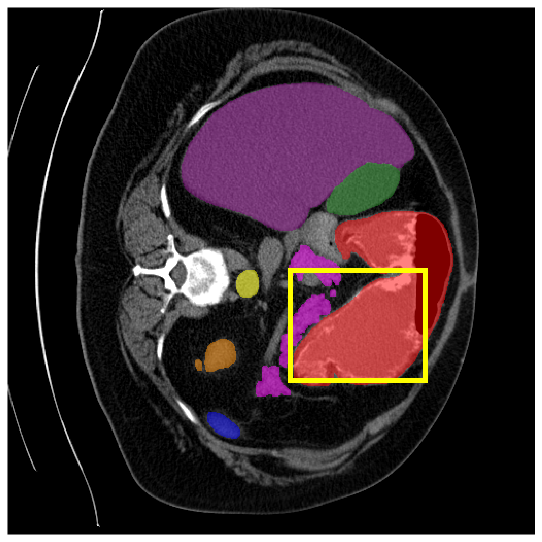

4.3.2 Visual Comparisons

Visualization of our method on the Synapse and ACDC datasets is shown in Fig. 3(a) and Fig. 3(b). For the Synapse dataset illustrated in Fig. 3(a), FCT failed to accurately segment SM and GB, while MERIT achieved precise segmentation of SM but struggled with GB. In contrast, our method achieved accurate segmentation of both SM and GB. Regarding the ACDC dataset shown in Fig. 3(b), while previous methods achieve comparable segmentation of the Myo and LV to the GT, they exhibit noticeable errors on the RV, including invasion into adjacent organs and misrecognition. On the other hand, our method accurately segments across all three structures Myo, LV, and RV, performing as precisely as the GT. We demonstrate the superiority of our method quantitatively and qualitatively.

To demonstrate the superiority of our method, additional qualitative comparison results for the ACDC and Synapse datasets are presented in Fig. 6, Fig. 7, respectively. Notably, in the case of GB, the quantitative results in Fig. 7 show relatively lower performance in ‘only ’. However, the visualization results in Fig. 7 reveal instances where the enhanced images identified GB regions that the original images failed to segment, albeit with some boundary over-segmentation. In such scenarios, our proposed method successfully leveraged the information from enhanced images to achieve more accurate GB segmentation. Note that this finding underscores the fact that even when quantitative performance metrics appear lower, the additional information provided by enhanced images can be valuable in the actual segmentation process.